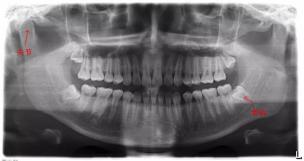

平时前往医院看牙时 , 相信大家都会有各种各样的疑惑:“看牙有必要拍X光吗?” , “X光辐射对身体有危害吗?” , “X光能查出什么 , 还是纯粹浪费钱”……下面将对一些普遍性的疑惑进行解答:

为什么要拍牙片?

拍牙片能够清楚、直观地了解牙齿目前的情况 , 有些牙医肉眼观察了许久都无法判断的病灶 , 可以通过牙片一眼就辨别出来 。 除此之外 , 牙片还可以对牙床位置有一个整体性的了解 , 便于医生制定后续整体性的治疗方案 。